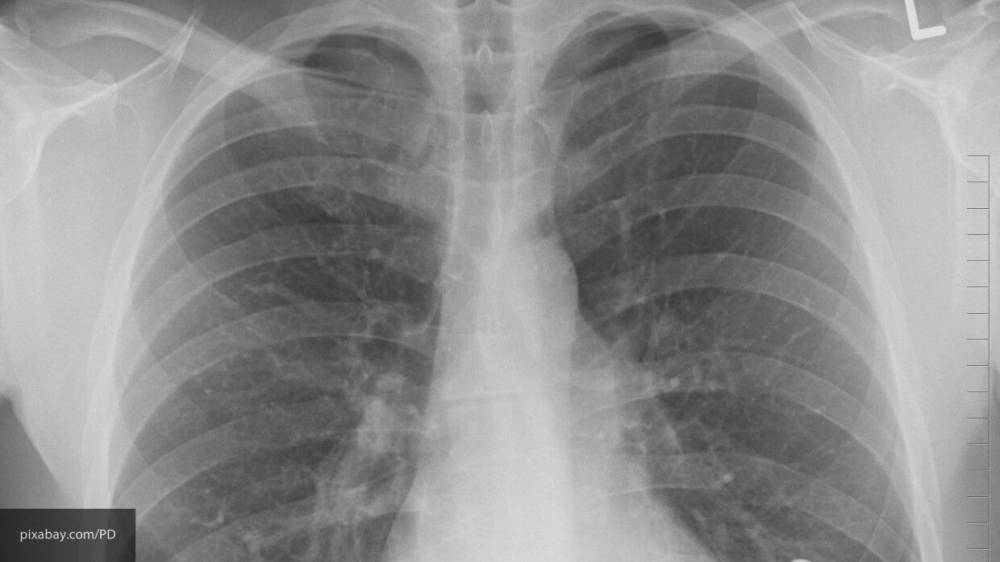

Как изменяются легкие у пациентов, умерших от СOVID-19 — исследование ученых

Международная группа исследователей изучила образцы тканей легких, полученные после вскрытия семи пациентов, умерших из-за коронавируса. Их сравнили с материалами больных, скончавшихся в результате острого респираторного дистресс-симптома, который проявляется при гриппе.

Исследование показало, что в легких пациентов с подтвержденным COVID-19 имеются определенные изменения, которые могут стать причиной многих тяжелых осложнений. Так, специалисты выявили в материалах признаки прогрессивных